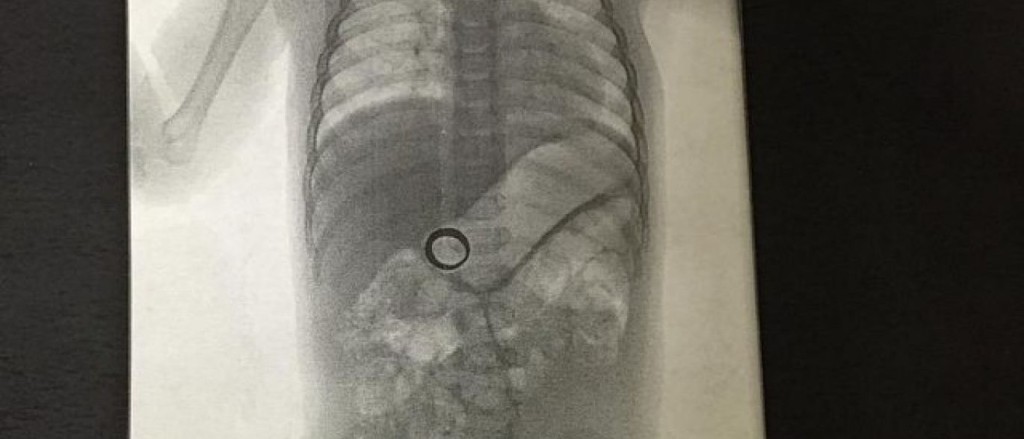

Uma mulher reclamou com o marido sobre o desaparecimento de sua aliança de casamento. O mistério acabou quando, chocada, descobriu que o objeto estava dentro de seu bebê. Segundo o portal “R7”, uma imagem de um exame raio-X revelou que a aliança desaparecida estava dentro da criança.

A foto foi postada no site Imgur por Clark Griswold, na última quinta-feira (28 de janeiro), e rapidamente se tornou viral. Junto da imagem ele disse: “Ontem a minha esposa não conseguia encontrar a aliança de casamento. Decidimos submeter nosso bebê ao raio-X para tirar as dúvidas.” O bebê passa bem, e Clark prometeu atualizar as informações logo que a criança “defecar” a aliança.